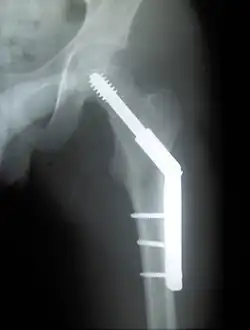

Dynamic hip screw (DHS) or Sliding Screw Fixation is a type of orthopaedic implant designed for fixation of certain types of hip fractures which allows controlled dynamic sliding of the femoral head component along the construct. It is the most commonly used implant for extracapsular fractures of the hip,[1] which are common in older osteoporotic patients. There are 3 components of a dynamic hip screw, including a lag screw (inserted into the neck of the femur), a sideplate and several cortical screws (fixated into the proximal femoral shaft). The idea behind the dynamic compression is that the femoral head component is allowed to move along one plane; since bone responds to dynamic stresses, the native femur may undergo primary healing: cells join along boundaries, resulting in a robust joint requiring no remodeling.

Fracture supported by dynamic hip screw